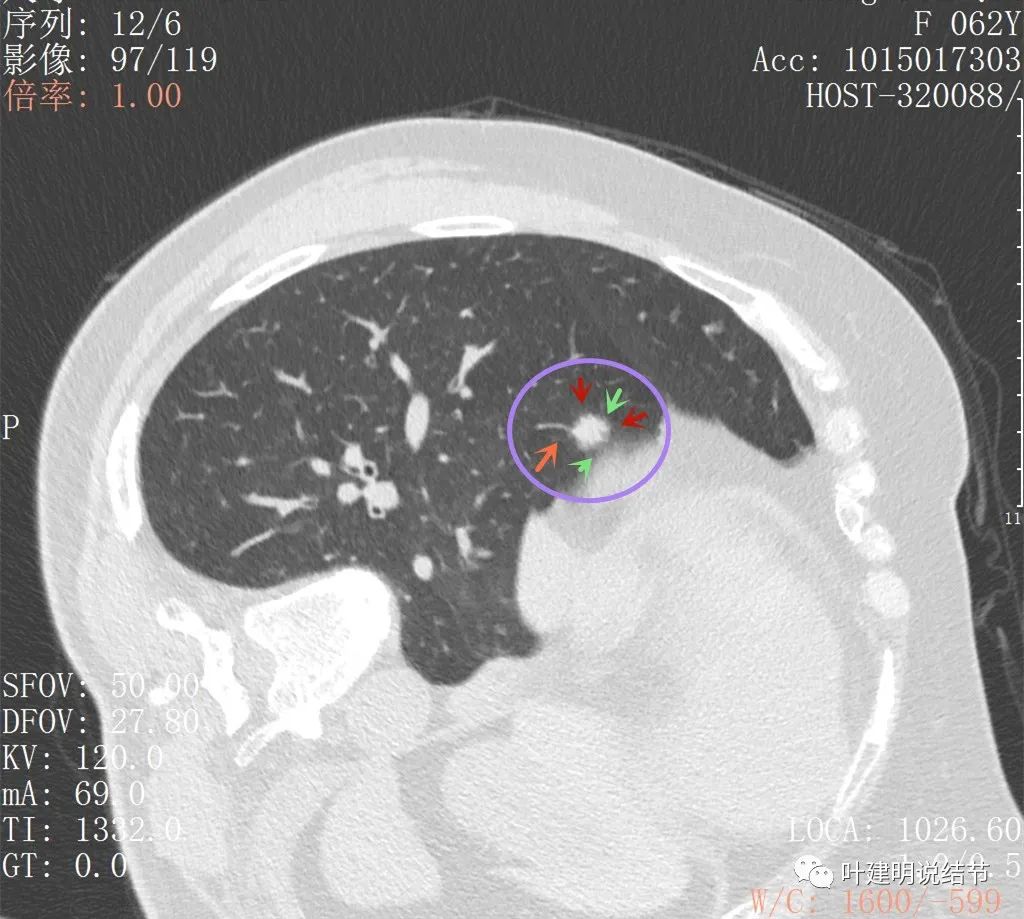

上图见病灶较为典型的恶性征象,边缘有细毛刺,也有少许磨玻璃(绿色所指),还有血管进入(桔色),总体上看,像颗杨梅

上图也是较为典型的恶性样子,有血管征,有边缘细锯齿状,且存在2年多不吸收好转,也不钙化或成疤痕样收缩

病灶似有毛刺,部分偏长